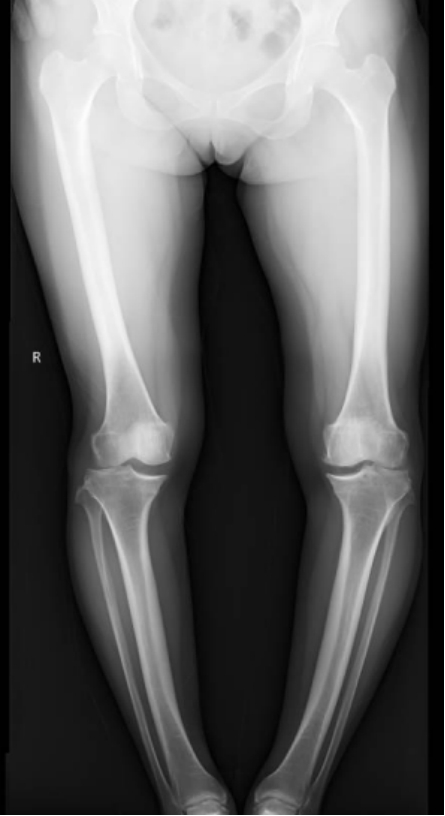

李彬在詳細(xì)了解了董阿姨的病史、進(jìn)行了全面的體格檢查和相關(guān)的輔助檢查后,組織科室進(jìn)行了深入的討論。最終的“答案”是——雙膝骨性關(guān)節(jié)炎、雙膝關(guān)節(jié)畸形、骨質(zhì)疏松以及雙膝半月板損傷。

面對(duì)這樣復(fù)雜且嚴(yán)重的病情,李彬并沒有退縮。他深知,對(duì)于董阿姨來說,這不僅僅是一次手術(shù),更是一次重生的機(jī)會(huì)。因此,他精心制定了手術(shù)方案:對(duì)雙下肢脛骨近端、遠(yuǎn)端以及雙側(cè)腓骨遠(yuǎn)端進(jìn)行截骨矯形,并進(jìn)行植骨內(nèi)固定。這樣的手術(shù)方案,無疑是對(duì)醫(yī)生技術(shù)的一次高難度挑戰(zhàn)!

手術(shù)前 手術(shù)后

2024年8月13日,手術(shù)順利進(jìn)行。

手術(shù)很成功!經(jīng)過精心的治療和護(hù)理,董阿姨在9月順利出院。當(dāng)她再次站在鏡前時(shí),她驚喜地發(fā)現(xiàn)自己仿佛長(zhǎng)高了一截,那份曾經(jīng)讓她備受折磨的疼痛與不適也逐漸消失了。